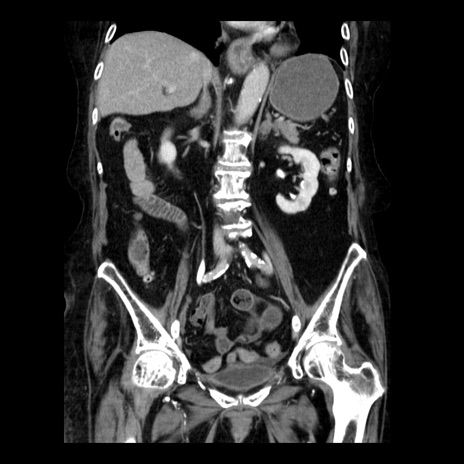

症例14(冠状断像)

【症例】 90歳代女性

【主訴】 腹痛・嘔吐

【現病歴】今朝から左側腹部痛を認めた。 経過観察していたが、嘔吐を認めたため来院。

【既往歴】 子宮癌術後

【身体所見】 意識清明、BP 127/54mmHg、P 98bpm Sp02 95%(RA)、BT 35.8°C、腹部平坦・軟腸ぜん動音聴取良好、右下腹部圧痛(+) 反跳痛なし

【データ】WBC 9800、CRP 0.46